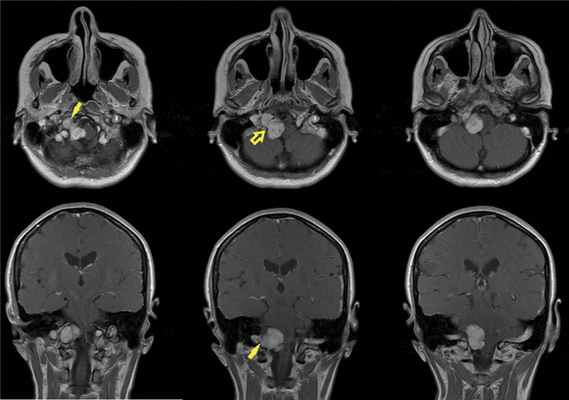

По данным МРТ головного мозга с усилением сигнала парамагнетиком выявлена опухоль парастволовой локализации справа, компримирующая продолговатый мозг и исходящая из расширенного канала подъязычного нерва. Меньший по размерам компонент опухоли располагался в полости канала и распространялся экстракраниально (рис. 1). Рис. 1. МРТ головного мозга пациентки В. до операции. При усилении сигнала выявляется опухоль справа, соответствующая невриноме, в форме «гантели», располагающаяся одной частью на уровне краниовертебрального перехода и вызывающая компрессию ствола мозга, а другой — частью в костных структурах.